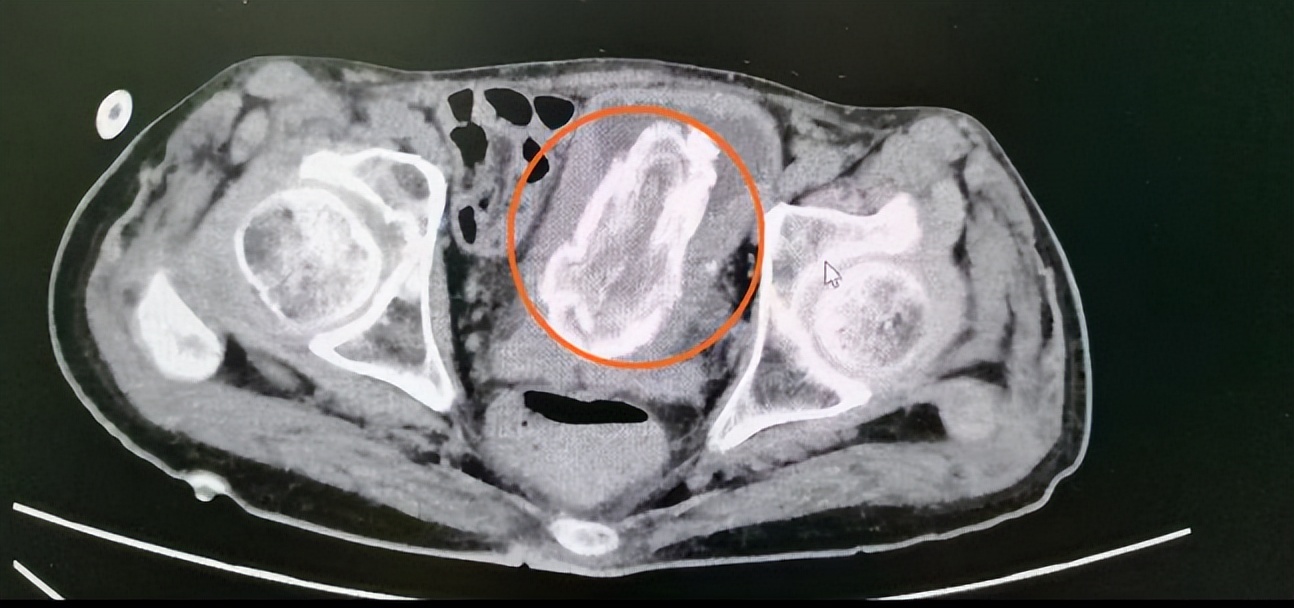

检查发现,57岁刘先生的膀胱有“巨大结石”。

在南医三院泌尿外科,刘先生接受了耻骨上膀胱切开取石术。术中可见, 膀胱内充满黄白色棉絮状物质,质软且松散,表面可见大量黄色结石附着。

原来,刘先生漏尿多年,因行动不便,经常瘫在床上,为防止漏尿弄湿床单,床上垫了隔尿垫。不知道从何时开始, 每当感觉要漏尿时,他就撕扯隔尿垫,将隔尿垫里面的吸水棉塞进尿道口,防止尿液漏出。

泌尿外科主任刘存东介绍,临床上确实会遇到不少因往尿道塞异物来就诊的患者,无论是出于什么原因,建议尽快戒掉这个坏习惯。 异物进入膀胱,它将作为核心使尿盐沉积于其周围形成结石,继而破坏膀胱的抗返流机制,使尿液逆流到肾脏,影响肾功能,导致肾积水等。